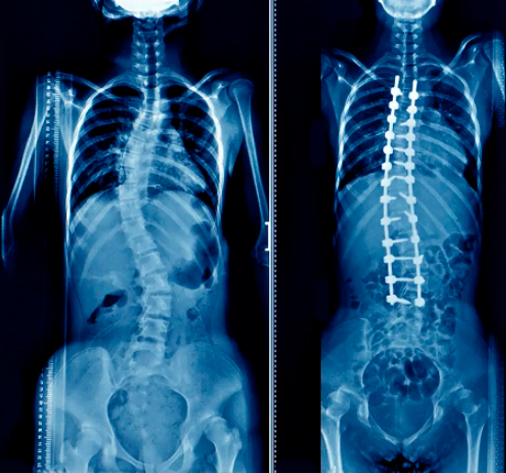

Correção de escoliose “S” idiopática dupla-curva